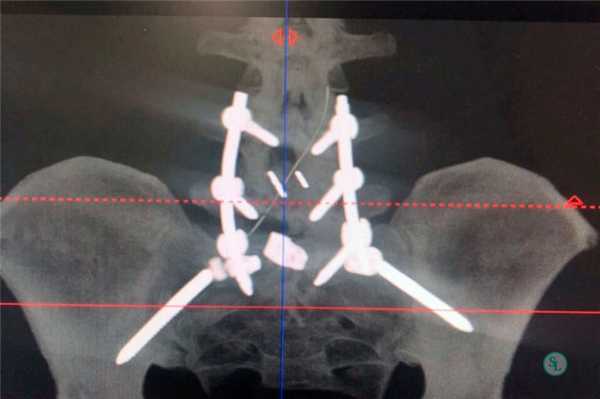

Системы стабилизации позвоночника жесткого типа

Жесткие, или неподвижные металлоконструкции подразумевают закрепление позвонков в постоянном фиксированном положении. Устанавливаются они из заднего доступа (со стороны спины) под контролем КТ и рентген-аппаратуры. Крепятся к позвонкам резьбовыми винтами, которые погружают в костные тела на глубину до 80%. Рекомендуют ставить подобного плана системы сугубо в безальтернативных случаях, если ни один другой вид лечения не сможет решить проблему с поврежденным отделом позвоночника.

Охарактеризуем самое распространенное средство неподвижной фиксации позвоночника - транспедикулярное устройство на примере системы «Криптон» (Krypton®). Это - востребованная модель ТПФ в спинальной нейрохирургии. Ее производит ведущая немецкая компания Ulrich Medical GmbH.

Стабилизация поясничного отдела.

Транспедикулярная фиксация позвоночника

Транспедикулярная фиксация или ТПФ - операция, при которой позвонки фиксируются и стабилизируются при помощи специальных имплантов (транспедикулярных винтов). В каждом позвонке есть точка ввода винта, которую установил в 1985 году Рой Камилл — это точка пересечения поперечного отростка позвонка с верхнем суставным отростком. С помощью специальных инструментов в эту точку, вкручиваются винты определяя анатомически правильное расположение позвоночника, тем самым излечивая заболевание. Первые попытки установки имплантов были в 60-70 гг. прошлого века и с тех пор является «золотым стандартом» в лечения переломов и различных заболеваний позвоночника.

ТПФ выполняется под рентгеновским контролем, что позволяет хирургу точно контролировать каждое движение и избежать повреждения близкорасположенных анатомических структур. Чаще для этого используется ЭОП или КТ.

Очень важно при установки винтов соблюсти следующие моменты: отсутствие пространства между костью и винтом, исключение травматизации нервных и сосудистых структур или смежных дугоотросчатых суставов. Импланты устанавливаются согласно размерной линейки каждого позвонка и винта, бикортикально не касаясь замыкательных пластин.

Точка установки винта в корень дуги подбирается на основании расположения двух анатомических ориентиров - поперечного и суставного отростков позвонка. Непосредственно позвонок перфорируют с помощью специального зонда.